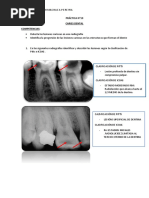

CLASIFICACION DE LAS CAVIDADES

Por el grado de afectación: Asociada a ICDAS II:

Código 3: Código 4:

Afect. dentina (oscura) cavidad en dentina

Mínima cavitación pequeña cavidad

cavit. esmalte o no superficial o media

del esmalte en esmalte

Código 5: Código 6:

cavidad en dentina cavit. profunda y

cavit. en dentina cavidad en dentina

media o profunda extensa en dentina

<50% superficie profunda

>50% superficie